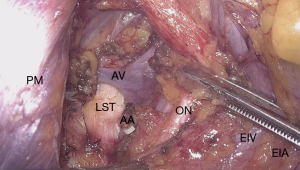

The neural evaluation starts with a correct definition of visceral and somatic pain. Visceral component of CPP requires a thorough understanding of the pelvic autonomic innervation. Visceral pain is diffuse, not well localized and it is conducted by the hypogastric plexus. Para-aortic sympathetic trunk forms the superior hypogastric plexus. Neurons descending down bilaterally join the pelvic splanchnic nerves to form the inferior hypogastric plexus. Both sympathetic and parasympathetic fibers of the hypogastric plexus are responsible for conduction of the nociceptive signals from the pelvic organs (94). Due to this autonomic innervation, visceral pain is also associated with symptoms such as malaise, bloating, nausea, vomiting and syncope. On the other hand, somatic pain is conducted by the lumbosacral plexus (L4–5, S1–5) and pathologies affecting the plexus or the somatic nerves origination from the plexus are responsible for well localized pain or loss of sensation at the lower abdominal wall, perineal region and lower extremities (95) (Figure 3).

In addition to a thorough anamnesis neurological examination also involves MRN and/or electromyography (EMG). A thorough surgical history has also utmost importance, because of possible nerve injuries. For instance, lateral trocar entrance areas proximal to the spina iliaca anterior superior are also where the ilioinguinal and iliohypogastric nerves originating from the lumbosacral plexus enter anterior abdominal wall. An injury sustained by the entrance of trocars during laparoscopy, can results in anterior abdominal wall pain. These nerves can also be injured during a herniation repair or by operations where a wide transverse skin incision is required (96). In addition, genitofemoral nerve is located on the psoas muscle and can easily be damaged during abdominal surgery (97) (Figure 4).